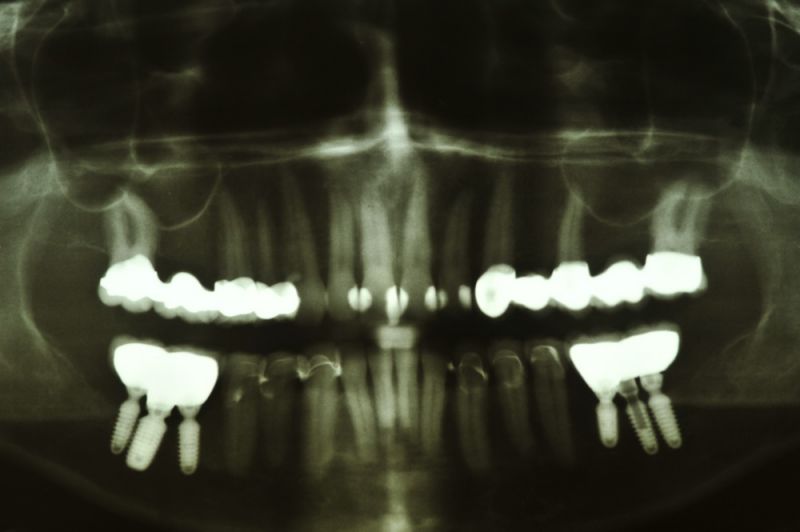

Es war eine Kombination aus Schmerzen bis an die Suizidgrenze, beschränkten wirtschaftlichen Möglichkeiten, sehr stark eingeschränkten Möglichkeiten der für Implantate zur Verfügung stehenden Knochenverhältnisse in einem stark atrophierten Unterkieferseitenzahnbereich und zudem dann auch noch durch auftretenden Problemen bei der Implantatinsertion und nachfolgenden Versorgung der Implantate.

Die Problematik der Implantatversorgungen kann man in einer Analogie folgendermaßen darstellen. Die räumlich beengten Zustände gleichen dem Tanz eines Paares auf einer Briefmarke, und der gleichzeitigen Schritt- und Fusshaltung, dass beim Tanzen die Schuhe geputzt werden können!